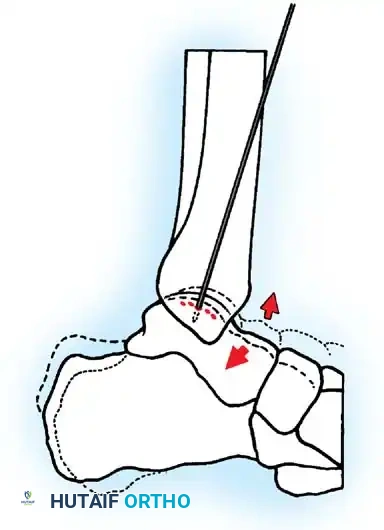

For lesions inaccessible via standard anterior portals, a transmalleolar approach is highly effective. The goal is to drill multiple holes in the crater to promote vascularization. These holes can be drilled transmalleolarly under direct vision through the arthroscope or with image intensification.

Fig. 42-49 Arthroscopic drilling of osteochondritis dissecans of talus. Single Kirschner wire through hole drilled in malleolus produces multiple holes in crater of talus when ankle is flexed at different degrees. (Redrawn from Guhl JF: New techniques for arthroscopic surgery of the ankle: preliminary report, Orthopedics 9:261, 1986.)

Step-by-Step Transmalleolar Drilling:

1. Targeting: An anterior cruciate ligament (ACL) or specialized ankle drill guide is introduced through the arthroscopic portal and placed precisely over the center of the talar defect.

2. Incision: A small stab incision is made over the medial or lateral malleolus, depending on the lesion's location.

3. Drilling: A 1.6-mm or 2.0-mm Kirschner wire (K-wire) is drilled through the malleolus, across the joint space, and into the talar defect.

4. Maximizing Perforations: Multiple holes can be drilled in the crater in the talus through one single hole drilled through the malleolus. This is achieved by keeping the K-wire trajectory constant while combining dorsiflexion and plantarflexion of the ankle (as illustrated in Fig. 42-49). This technique minimizes iatrogenic damage to the malleolar articular surface while maximizing the surface area of marrow stimulation within the talar defect.

5. Depth: The K-wire should penetrate approximately 10 to 15 mm into the subchondral bone to ensure adequate access to vascular marrow.

- Malleolar Fracture: When performing transmalleolar drilling, multiple passes through the malleolus can create a stress riser. The technique of using a single malleolar hole while flexing/extending the ankle (Fig. 42-49) mitigates this risk.